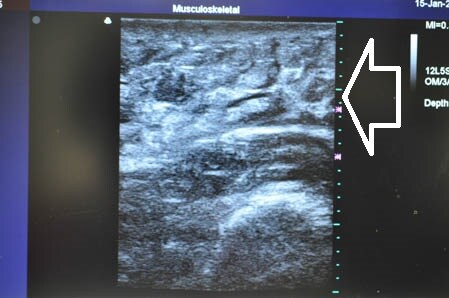

右二の腕。

↓ ↓ ↓

左二の腕。